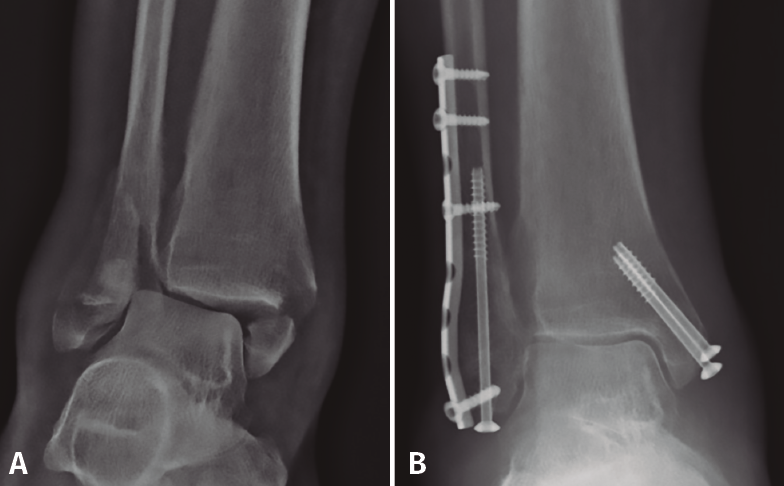

Respecto a esta técnica, debemos diferenciar 2 conceptos: por un lado, el uso de tornillo intramedular percutáneo aislado, con el beneficio de menores complicaciones de partes blandas. Pero, por otro lado, esta técnica puede usarse combinada con la osteosíntesis convencional como método para aumentar la estabilidad de la construcción (Figura 5), tanto con el uso de tornillo intramedular (a través o fuera de placa) como con el uso de agujas de Kirschner endomedulares. Koval(56) realiza un estudio clínico y biomecánico demostrando el beneficio de añadir 2 agujas de Kirschner endomedulares a la osteosíntesis convencional para el tratamiento de fracturas osteoporóticas y conminutas. En el estudio biomecánico, la resistencia al doblado aumentaba en un 81% y la resistencia a la torsión era del doble, al añadir las 2 agujas de Kirschner de 1,6 mm en comparación con la placa aislada. En el estudio clínico, presenta una serie de 19 pacientes mayores de 50 años con osteopenia y/o conminución tratados con esta técnica, con correcta consolidación en todos los pacientes. Entre las complicaciones, 2 pacientes precisaron retirada de material (uno por migración de las agujas) y un paciente diabético presentó retraso en la cicatrización de la herida(56).

Figura 5. Placa de tercio de caña con refuerzo de tornillo intramedular (canulado de 4,0 mm).